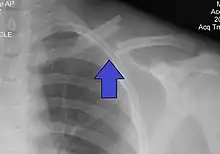

X-ray of a left clavicle fracture

The basic method to check for a clavicle fracture is by an X-ray of the clavicle to determine the fracture type and extent of injury. In former times, X-rays were taken of both clavicle bones for comparison purposes. Due to the curved shape in a tilted plane X-rays are typically oriented with ~15° upwards facing tilt from the front. In more severe cases, a computerized tomography (CT) or magnetic resonance imaging (MRI) scan is taken. However, the standard method of diagnosis through ultrasound imaging performed in the emergency room may be equally accurate in children.[5]